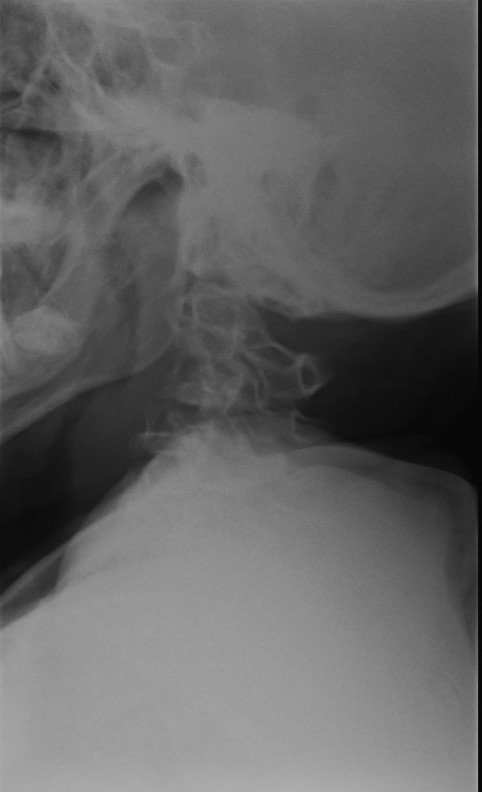

« MPS IV (MORQUIO-BRAILSFORD SYNDROME)